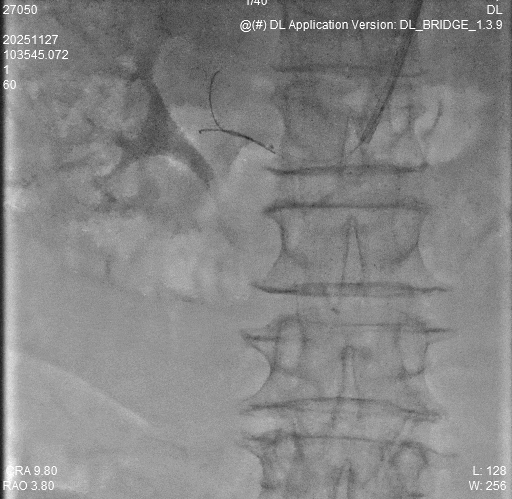

1. 患者仰卧位,左手内旋自然状态置于腹部,左手弯向病人的右腹股沟,左上肢常规消毒铺巾,暴露左手。左侧鼻烟壶处注射2ml利多卡因,使用微穿针以改良的Seldinger法向左侧远桡动脉动脉搏动最强处穿刺,穿刺成功后先置4F短鞘,将猪尾导管选至降主动脉后引入加硬导丝,再交换引入Cordis 6F薄壁长鞘。

2.导管配合0.035导丝进入腹主动脉下端,造影示:腹主动脉走形迂曲,血流通畅,右肾动脉主干起始段重度狭窄>90%,远端及分支显影浅淡。

3.换鞘管后引入导丝及导管置于右肾动脉开口处,冒烟确定右肾动脉位置,换0.014in及0.018in导丝通过狭窄段后置于右肾动脉远端分支,经导丝引入3*40mmPTA快速交换球囊预扩狭窄段。

4.导丝支撑下交换引入CWB60605L-18震波球囊扩张右肾动脉狭窄段,完毕后复查造影示右肾动脉通畅,血管残余狭窄<20%,扩张效果满意,术毕。